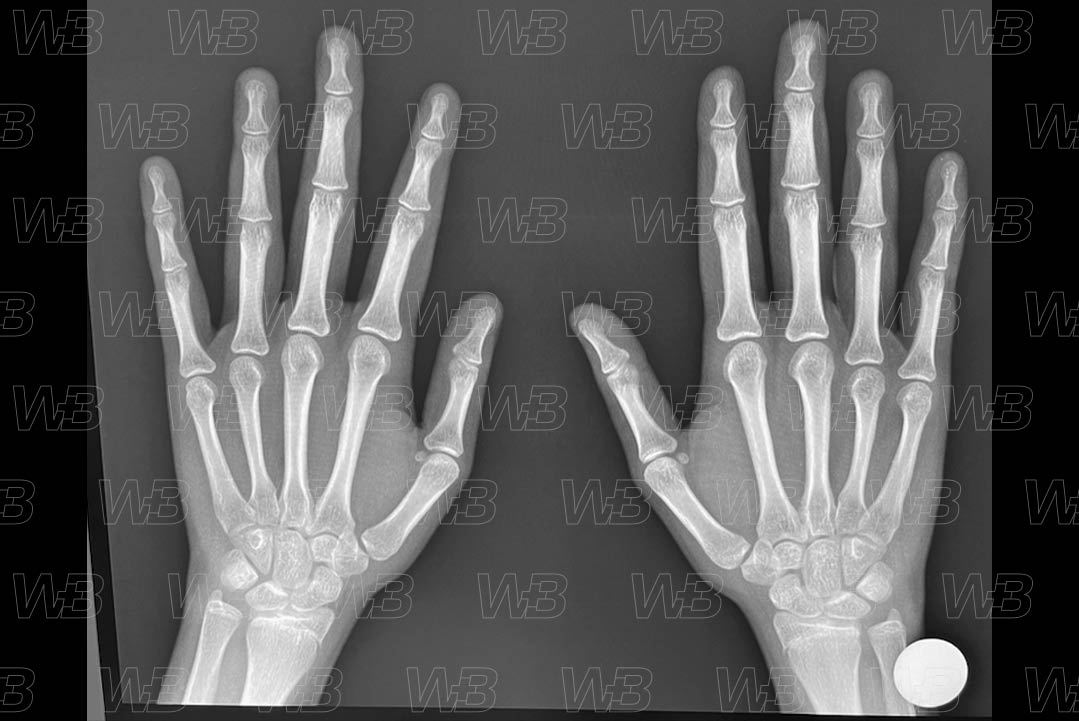

RADIOGRAFIA MÃOS E PUNHOS

Feminino

16 anos:

• Inicia-se a fusão do rádio.